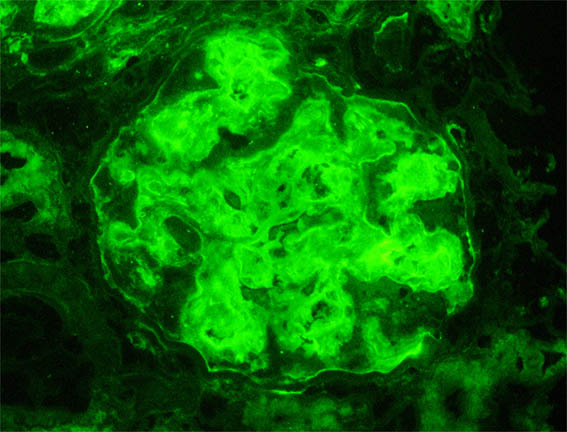

Figura 7. Inmunofluorescencia para IgG, X400.

Figura 8. Inmunofluorescencia para cadenas ligeras kappa, X400.

Figura 9. Inmunofluorescencia para cadenas ligeras lambda, X400.

Inmunofluorescencia directa para IgA, IgM, C3 y C1q: Negativas.